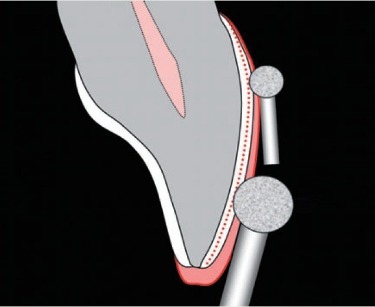

儘管瓷牙貼面和牙冠都可用於解決許多相同的牙齒美學問題,但通常這兩種治療方法是在不同情況下使用。 由於瓷貼面設計為僅覆蓋牙齒的前部可見部分,因此它們通常更適合用在堅固健康的牙齒上,因為對牙齒造成的傷害更小。 相反,全瓷牙冠是用來“蓋住”整顆牙齒的,提供結構和美學修復。 因此,全瓷牙冠通常是用來治療已經嚴重損壞的牙齒。

雖然磨牙為陶瓷貼片必要的過程,但可以透過顯微微創磨牙技術,將磨牙量控制在 0.3 ~ 0.5 mm,相較傳統作法的全瓷冠可保留超過 6 ~ 7 倍以上的牙齒琺瑯質。